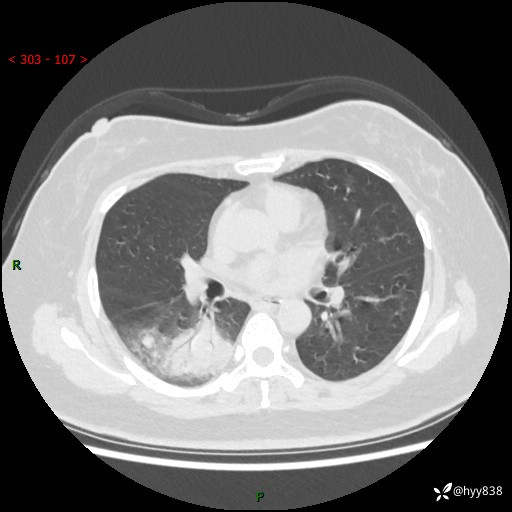

大叶性肺炎的表现形式,晒晒鉴别诊断吧…结果公布~

简要病史:患者8天前无明显诱因出现咳嗽、咳痰,为绿色脓痰,无明显加重与缓解因素,无高热、寒战,无呼吸困难,无大量脓痰,无哮鸣音,于当地医院行胸片示右下肺团块影,性质待定,予口服药物治疗症状未见明显改善,具体药名不详,为求进一步诊治来我院就诊,门诊以“肺占位性病变”收入我科进一步诊治。 患者自发病以来,精神、饮食尚可,睡眠欠佳,大小便正常,体力、体重未见明显异常。

辅助检查:CT

临床诊断:肺占位

胸部CT平扫